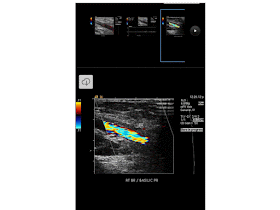

The majority of deep venous thromboses occur in the lower extremities and begin in the soleal veins of the calf. Doppler compression sonography is the imaging modality of choice.

• absent colour flow: if completely occlusive